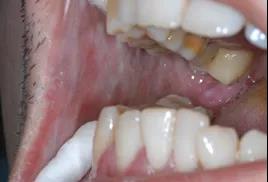

口腔黏膜下纤维性变是一种以炎症和渐进性黏膜纤维性变导致进行性张口困难为特征的口腔慢性疾病,具有癌变倾向,与口腔鳞状细胞癌发生密切相关,其恶性转化率为7-13%。该病的发生是多种因素共同作用的结果,咀嚼槟榔是其最主要病因。

患者最常见的症状为:

1、口腔黏膜灼痛感、刺激痛;

2、口干、味觉减退、唇舌麻木、黏膜水疱、溃疡等;

3、黏膜苍白、出现纤维条索;

4、进行性张口受限、吞咽困难等。